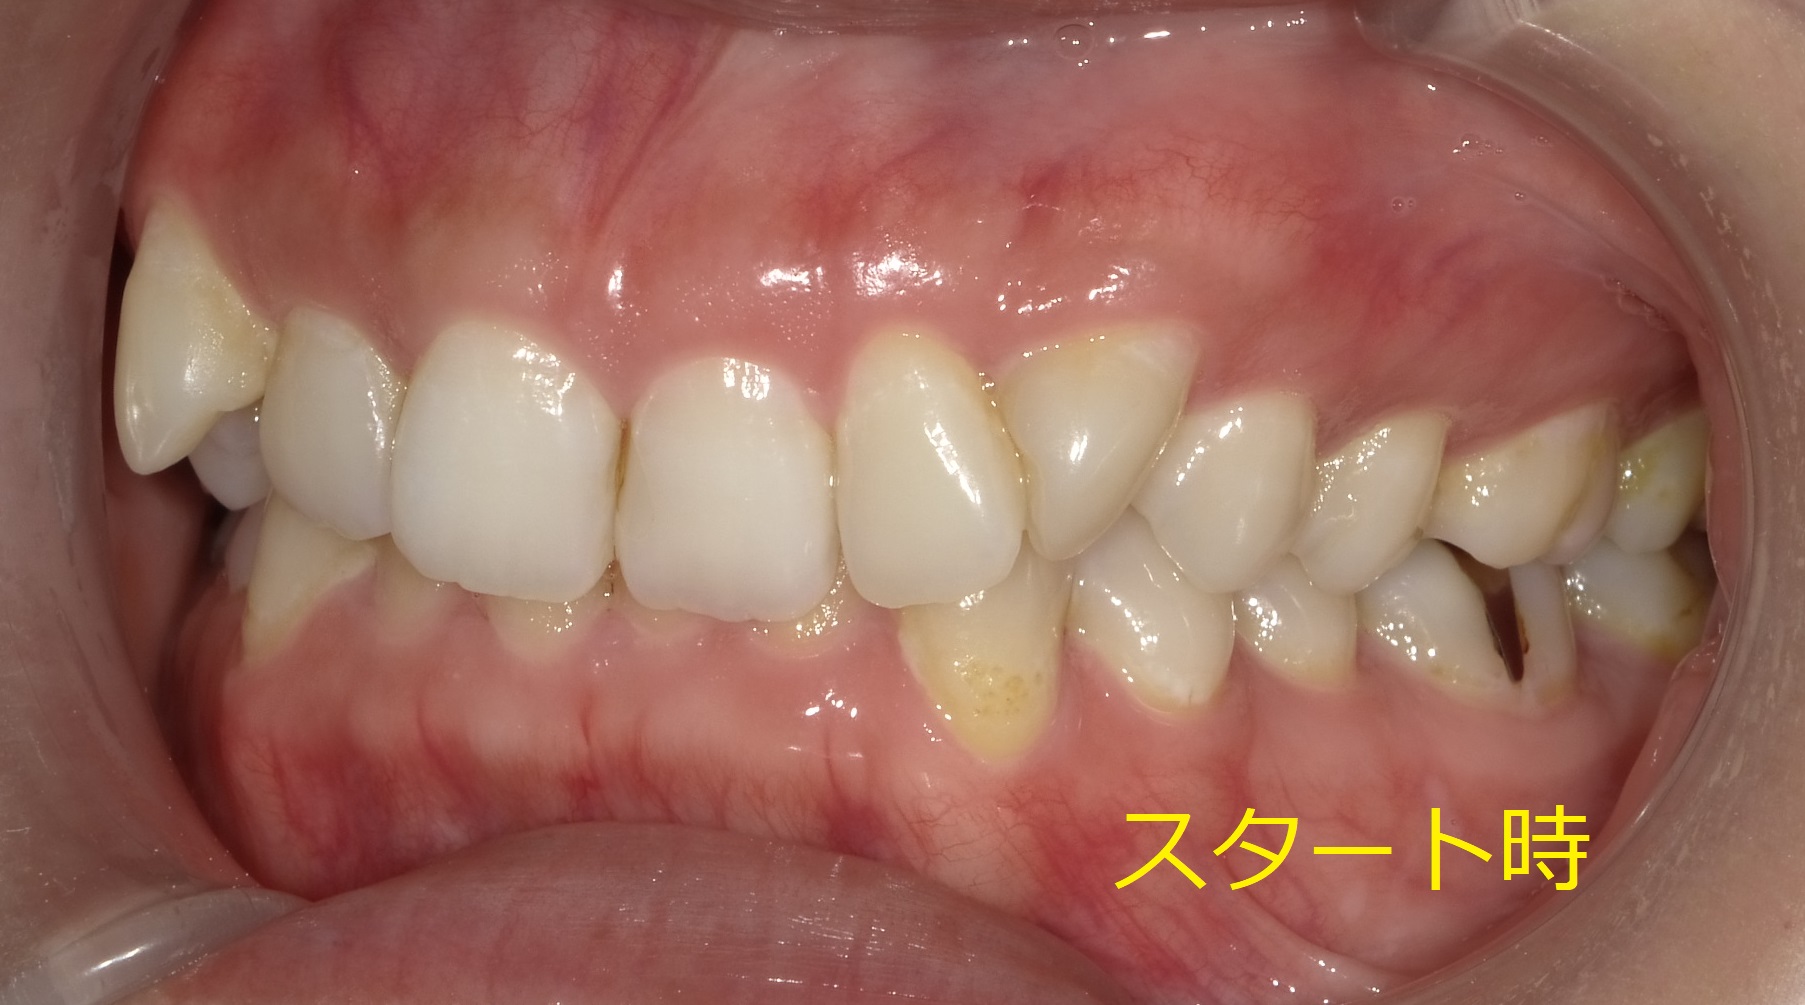

初診時の正面からの写真です。

上の八重歯の回転と全体的なバラつきが目立ちます。

当面の目標は上の歯の並びを整え、見た目を改善すると同時にかみ合わせを挙げ下の前歯が見えるようにしていきます。

(下の歯が見えてくることによって前歯の存在感、違和感を消すことができます。)